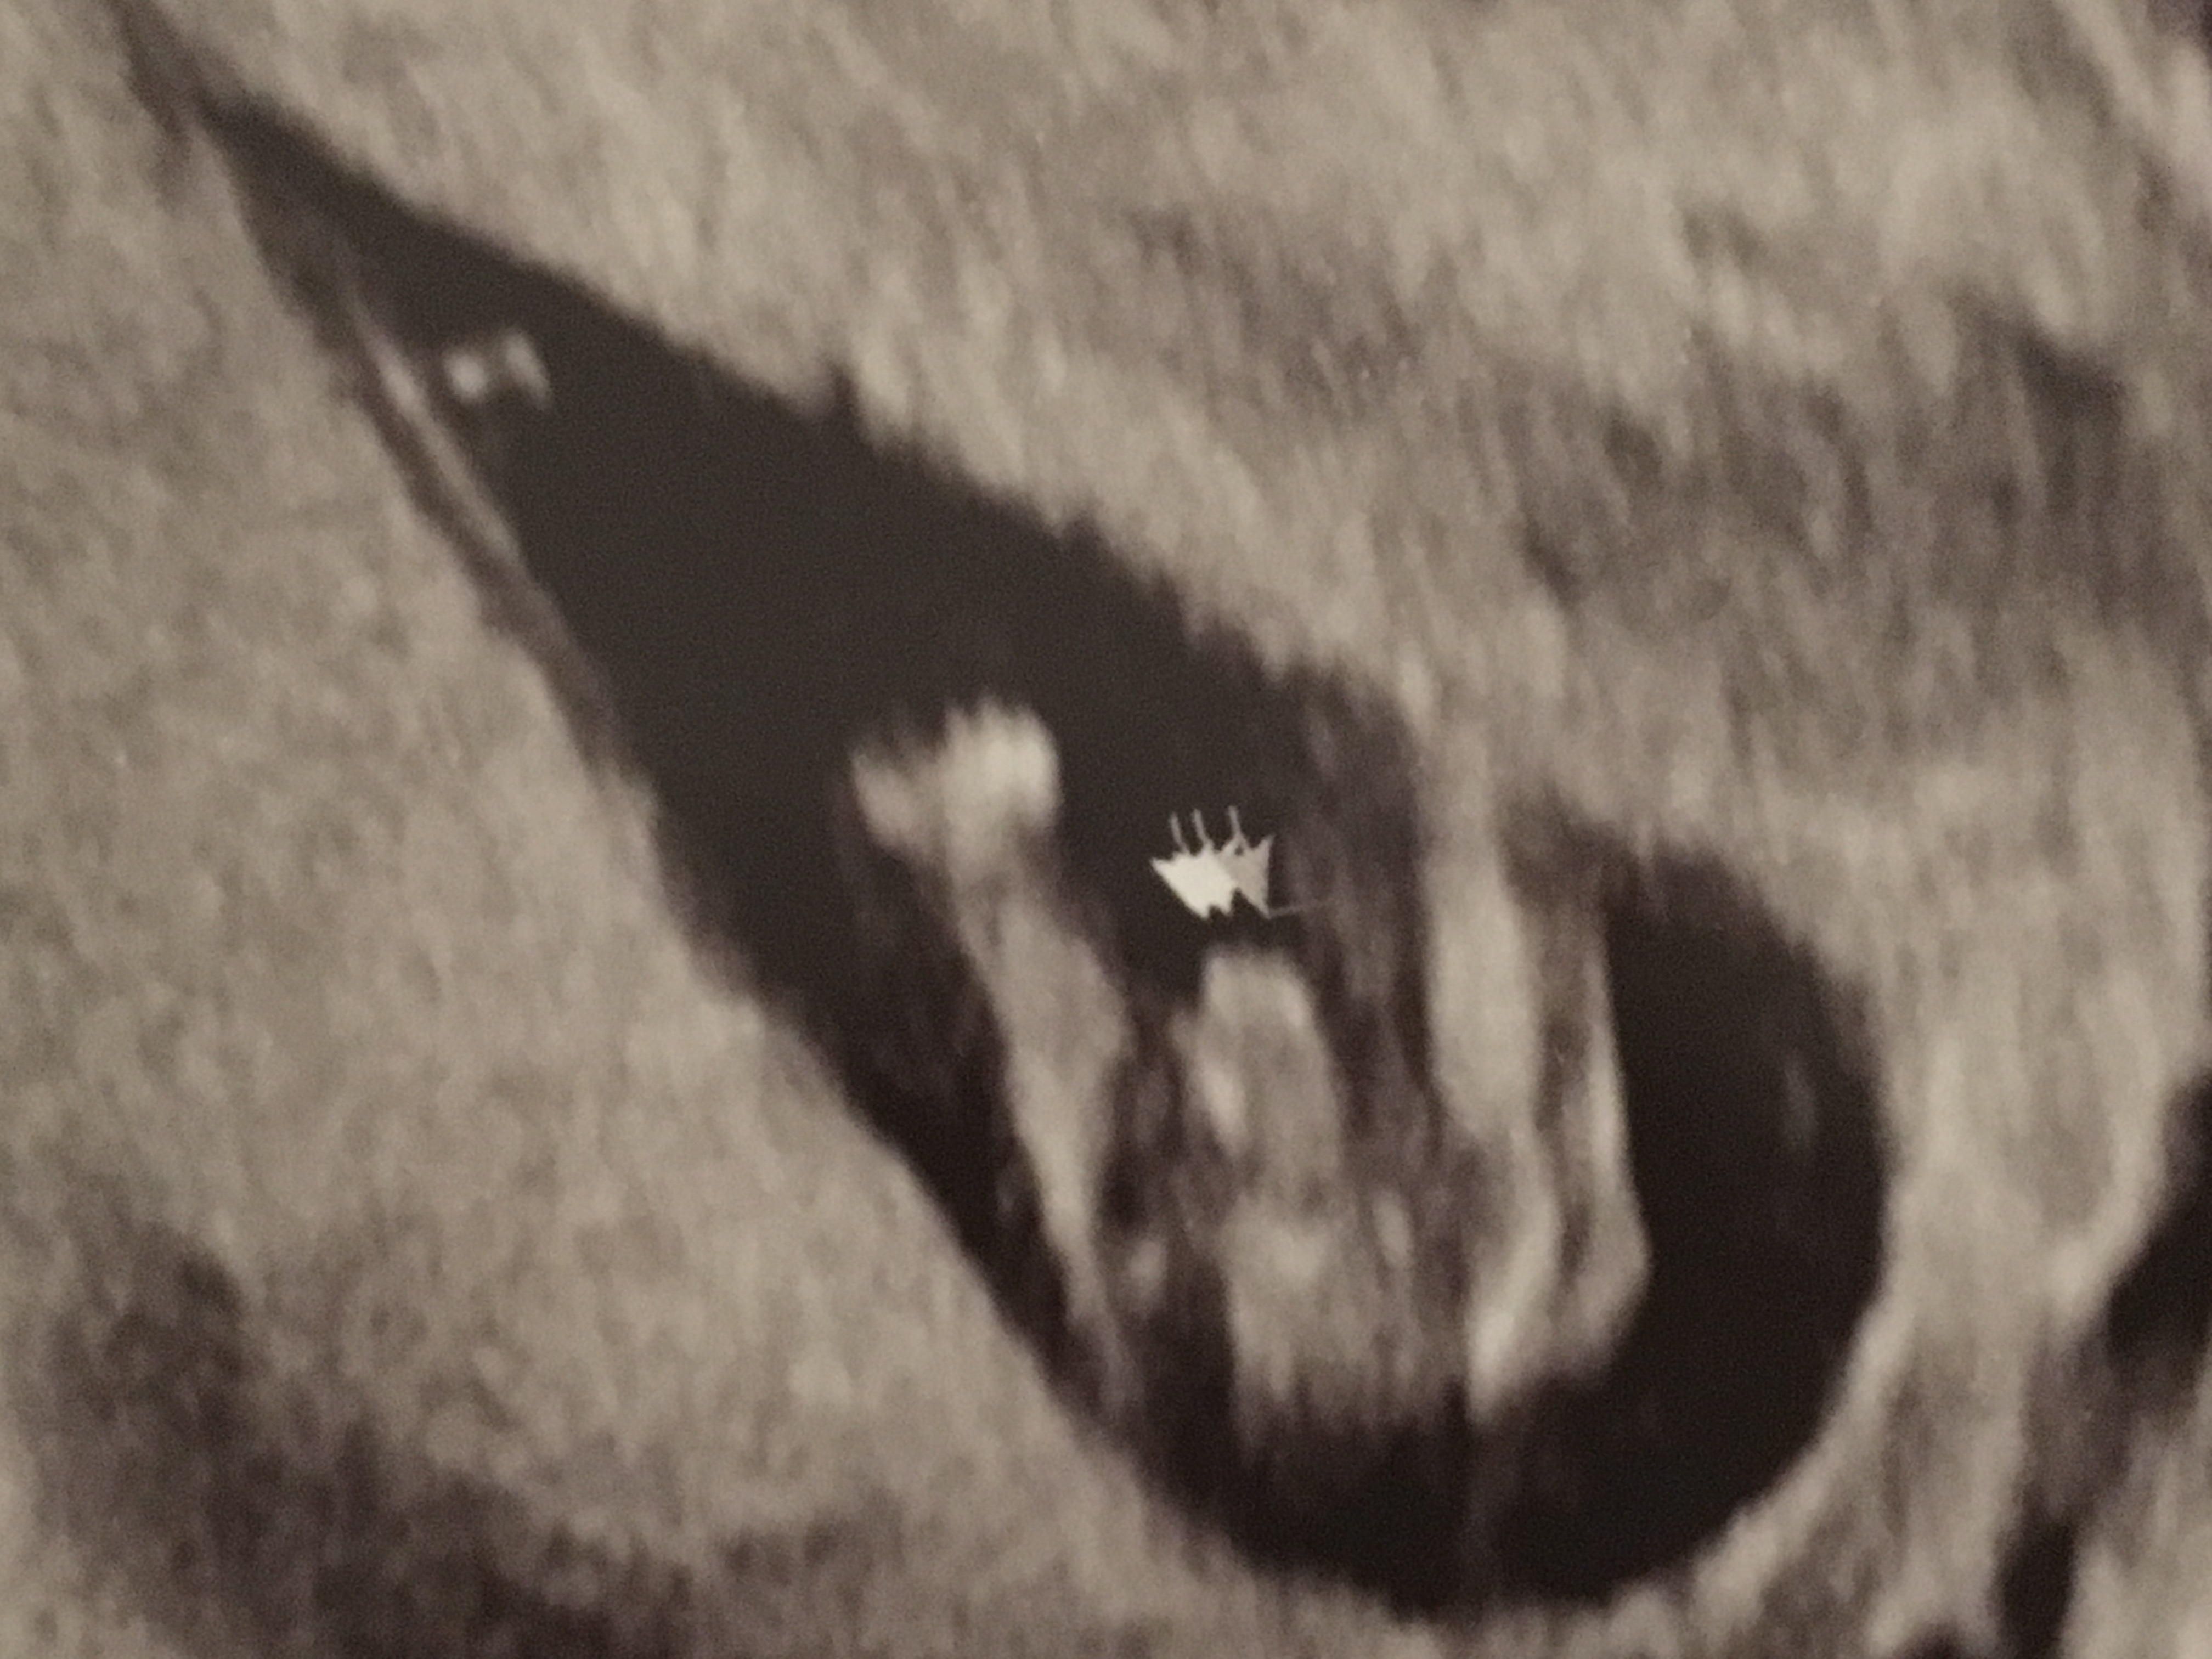

Not 100% sure if this is a nub or not. If it is, it looks boyish to me. All potty shots look clearly girl with 3 lines and no protrusion whatsoever. With my las pregnancy saw a clear penis protrusion at 13 weeks potty shot. Curious to get some feedback :) Attachment 33904Attachment 33905Attachment 33906

Very boyish :) The potty looks boyish too, boys can have 3 lines as well. I would say 99.9% boy.